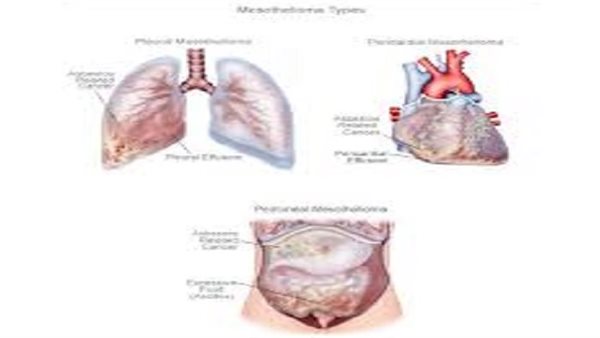

أسباب ورم المتوسطة الخبيب.. يعد ورم المتوسطة الخبيث من أنواع السرطان النادرة والخطيرة، ويصيب الطبقة الرقيقة التي تغلف الأعضاء الداخلية في الجسم، مثل: الرئتين والبطن والقلب.